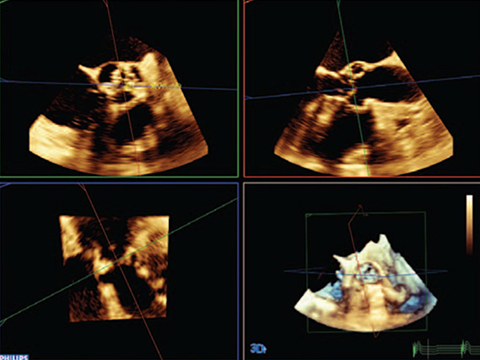

EPIQ CVxは、飛躍的に進歩した機能をもつ循環器用超音波診断ソリューションです。処理能力の向上、優れた鮮明さと高い分解能による卓越したイメージング、検査効率の改善、アナトミカル・インテリジェンス(AIUS)による堅牢で再現性の高い新たな定量化手法により、より良い検査を行うためにサポートします。

EPIQ CVxiはインターベンションエコーガイダンスの新しい方向性を示す製品です。要求の高い今日の医療課題を克服するため、多様な患者およびインターベンション手技に対応する高いレベルの臨床性能を備えています。装置上から直接、新しいEchoNavigator R3を操作することができ、ライブフュージョンイメージングの新しい合理化されたワークフローを実現します。